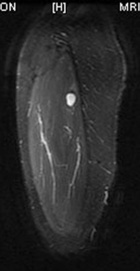

40 year old female presents with c/o burning/stabbing pain in her R anterolateral thigh. Pain has been present intermittently for >15 yrs, but has recently increased in intensity and frequency.

Zoom image: Radiological image Radiological image.